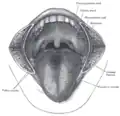

Vue bouche ouverte pour l'évaluation du grade de Malampati.

Vue bouche ouverte pour l'évaluation du grade de Malampati. Coupe sagittale du larynx et de la trachée